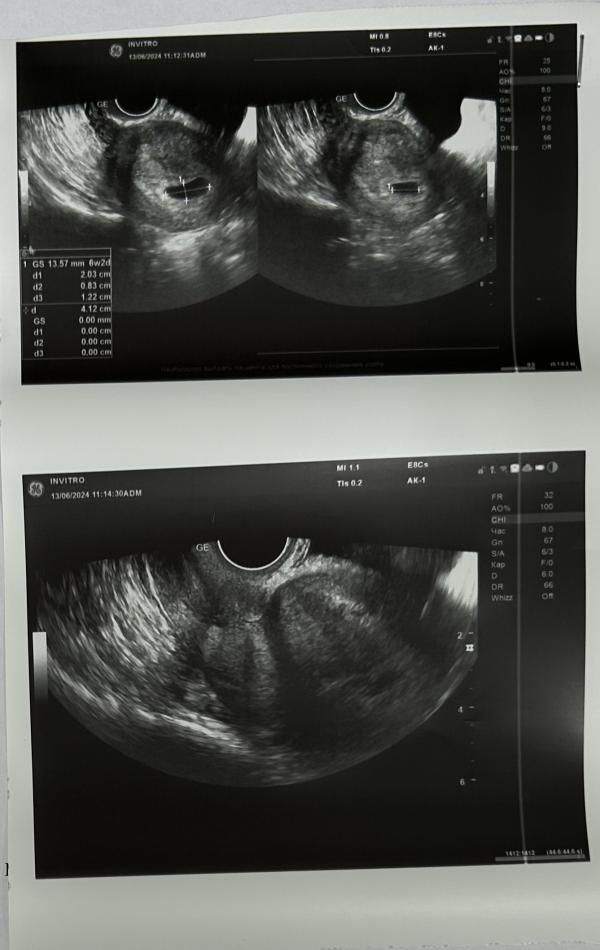

Плодное яйцо на месте, теперь ждём, когда будет видно эмбриончик и сб 💓

По ДПМ срок 6,1, по размеру плодного яйца 6,2.

Но скорее всего это погрешность и его просто расплющило из-за тонуса 👀